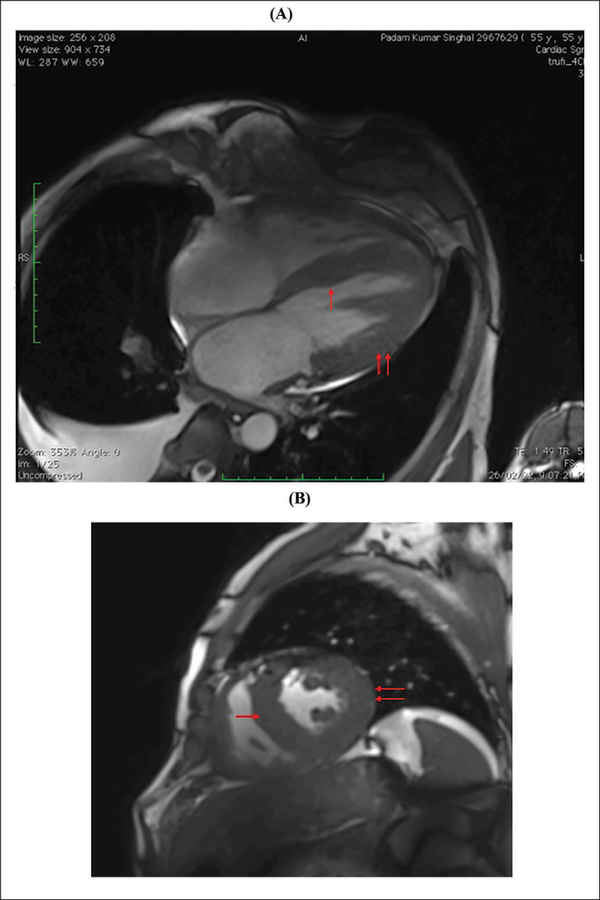

(A and B) Cardiac MR Showing Diffuse Thickening of Both Ventricles and Interventricular Septum (Red Arrows, Respectively).

Note: MR, magnetic resonance.

A clinical diagnosis of chronic congestive heart failure was made, and the patient was started on diuretics and investigated. Creatinine was 1.57 mg dl−1 with normal complete blood count and liver function tests (Table 1). Cardiac biomarkers revealed hs-tropI—383.7 ng l−1, Ck-MB—20 IU l−1, and NT-proBNP—8665 pg ml−1. Electrocardiogram (ECG) showed low voltage complexes in arm leads (Figure 1). Two-dimensional echocardiogram (2D ECHO) findings showed marked concentric left ventricular hypertrophy (LVH), LVEF—60%, abnormal global longitudinal strain pattern (apical sparing of longitudinal strain pattern), and cherry on top appearance. A low voltage ECG with concentric LVH and apical sparing of longitudinal strain pattern on 2D ECHO were suggestive of cardiac amyloidosis. A cardiac magnetic resonance (CMR) was done, which showed diffuse thickening of both ventricles, interatrial septum and interventricular septum, with reversal of the nulling pattern on T1 scout, with the diffuse enhancement of the walls of the thickened ventricles (Figures 2a,b and 3). A workup for primary amyloidosis was done. Serum immunofixation electrophoresis showed a monoclonal band in the beta region in the reference lane corresponding to lambda-only light chain, suggestive of light chain-only gammopathy (Figure 4). Free light-chain assay done showed involved FLC (lambda): uninvolved FLC (kappa) ratio was 14.01. iFLC was 835 mg l−1. dFLC was 775.39 mg dl−1. Serum B2 microglobulin was 5.39 mg l−1 (raised, cutoff—2.34 mg l−1). Total IgG was 14.06 mg l−1 (normal), IgA was 3.86 mg l−1 (normal), and IgM was 0.52 mg l−1 (normal). Flow cytometry immunophenotyping showed about 0.7% lambda-restricted abnormal plasma cells with reduced CD81 and aberrant CD28 expression. Bone marrow aspirate and biopsy were done, which showed trilineage hematopoiesis with myeloid preponderance and increased eosinophils and their precursors; plasma cells constitute about 5.5% of total nucleated cells with no evidence of amyloid deposit in the biopsy. A confirmatory diagnosis required a pericardial biopsy, but the patient refused for the same in view of the risk of adverse events. With cardiac ECHO/CMR findings and free light chain assay, a final diagnosis of AL-type cardiac amyloidosis, restrictive cardiomyopathy and heart failure with preserved ejection fraction (LVEF - 60%), on a background of chronic kidney disease, type 2 diabetes mellitus and hypertension was made. The patient was treated with intravenous Bortezomib (2 mg), Cyclophosphamide (300 mg) and Dexamethansone (40 mg). The patient showed clinical improvement and was discharged but was lost to follow-up.

Diagnosis of cardiac amyloidosis is often missed as it requires a high index of suspicion and low incidence overall. Laboratory tests, electrocardiography, cardiac imaging, and biopsy are required for making a diagnosis. Cardiac amyloidosis ECG pattern includes low voltage in limb leads (46%), due to electrically silent amyloid fibrils, and pseudo-infarct pattern (47%). Some ECGs may also depict arrhythmias, such as atrial fibrillation, AV blocks, and bundle branch blocks. Symmetric biventricular thickened wall with a spectrum of diastolic abnormalities (varying from abnormal relaxation to a restrictive filling pattern) is the hallmark of amyloidosis on 2D ECHO., , In cases where LV wall thickness is >12 mm without any history of hypertension, suspicion of cardiac amyloidosis should be kept high. Left ventricular ejection fraction is usually not affected till a later period in the disease course., As the longitudinal strain decreased on basal and mid-wall segments of the heart as compared to the apex, ECHO shows a pattern of apical sparing pattern, which is specific for cardiac amyloidosis. CMR is a better choice of investigation as it identifies the early stage of a diffuse subendocardial pattern of gadolinium enhancement and the late stage of transmural myocardial enhancement. These changes start to occur before the development of LVH., Mandatory investigations, in a patient with suspected amyloidosis, include serum and urinary protein electrophoresis and immunofixation to identify monoclonal protein., ,